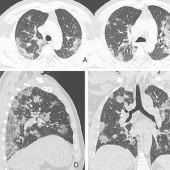

What do the lungs affected by coronavirus look like

Shocking X-rays of a 44-year-old patient from China who died from coronavirus show what this disease does to human lungs. We are ...